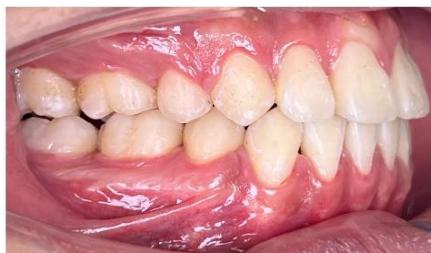

Figure 9: Re-leveling and alignment phase following anterior space closure of the four incisors

The patient was retained for three months prior to appliance removal. The total treatment duration was 33 months.